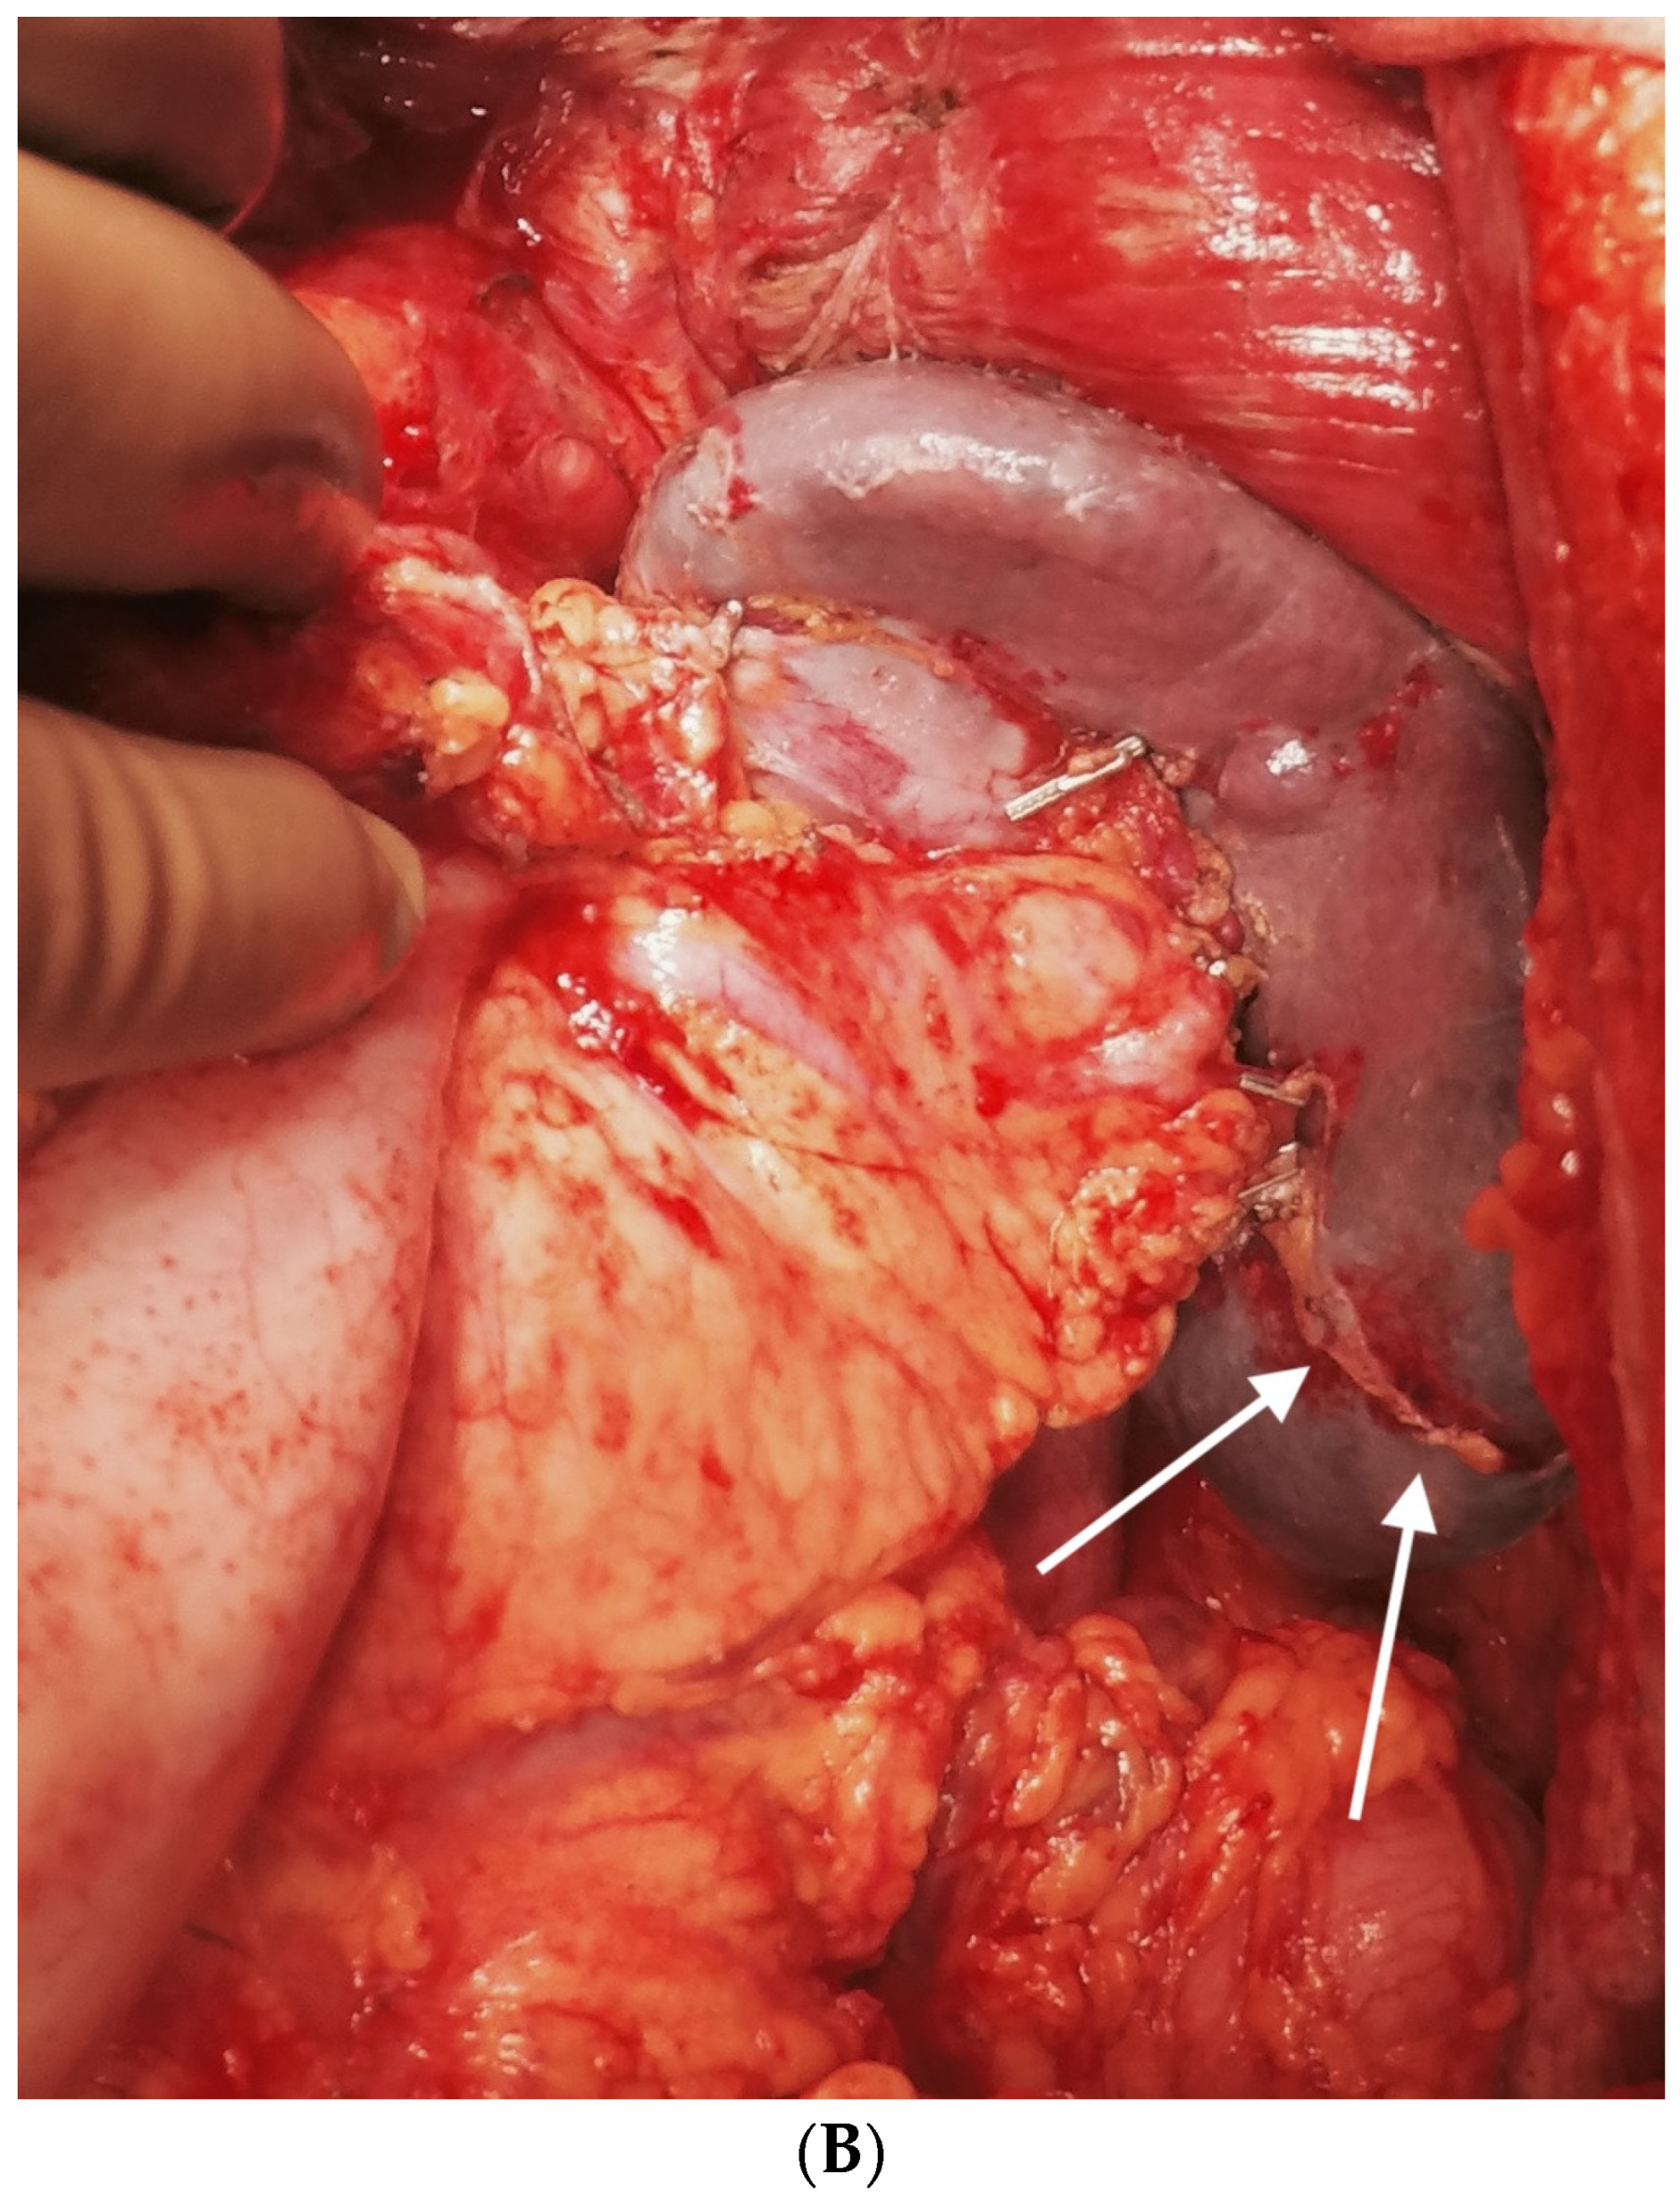

6.5. Lesser Omentectomy and Hepatoduodenal Ligament Clearance

6.6. Foramen of Winslow and the Posterior Layer of the Hepatoduodenal Ligament